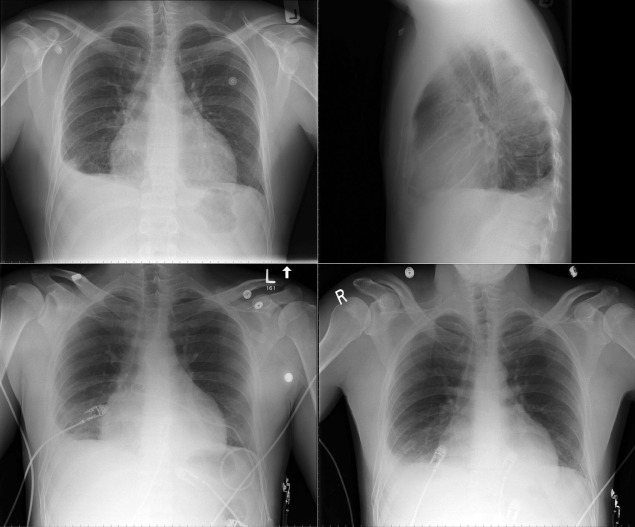

In constrictive pericarditis ( Graphic 16-1 ; Figs. 16-16 to 16-23 ) , the CPS is usually nonspecifically and mildly enlarged. Occasionally, the heart is normal or small in size. The left atrium is the most frequently enlarged chamber, because its enlargement is less restricted by pericardium. The right atrial contour on the frontal chest radiograph may be flattened. Calcification of the pericardium suggests past tuberculosis, but since tuberculosis has become uncommon at most centers, 90% of cases of constrictive pericarditis are currently noncalcified. Calcification, especially diaphragmatic, is not specific for constrictive physiology; it may be seen in the absence of cardiac compression. The apical surface is less frequently calcified than the interventricular and atrioventricular grooves. The apex seldom calcifies prominently in constrictive pericarditis; this finding suggests a calcified apical aneurysm rather that constrictive pericarditis.